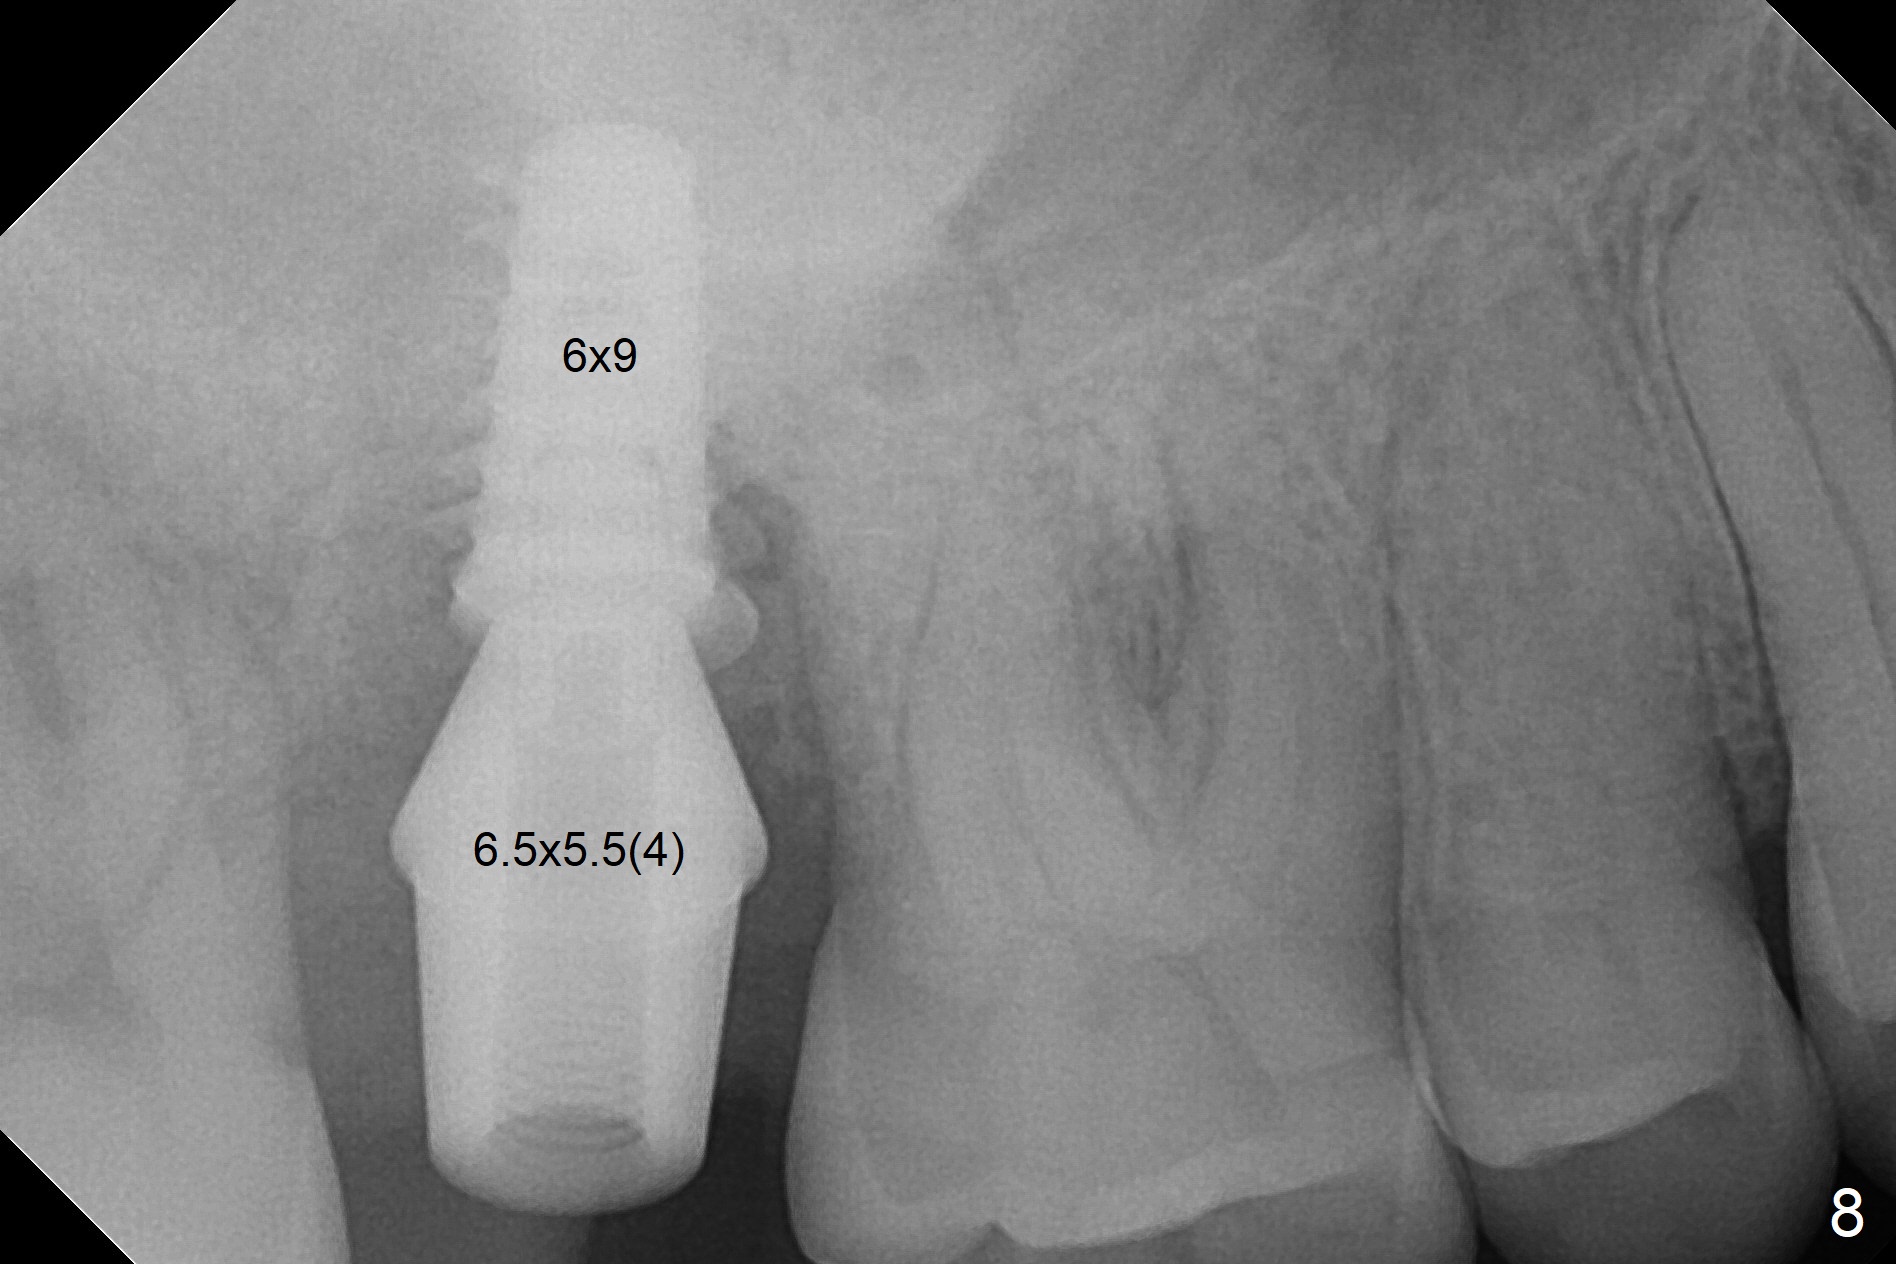

When the 59-year-old man returns for #24 implant placement, the tooth #2 is found to have crack (Fig.1,2 arrowheads), associated with buccal and palatal fistulae (*) and loss of amalgam (Fig.4 *). Abundant granulation tissue is attached to the roots of the affected tooth (Fig.3), indicating severe bone loss. There is a plateau associated with the septum and buccal sockets, which is the site of osteotomy. Magic split and 3 and 3.8 mm Magic Expanders are used to initiate osteotomy. After use of 4.3 mm Magic Drill for about 3 mm, Osteogen plug and allograft are used for sinus lift, followed by insertion of a 4.5x11 mm dummy implant (Fig.5). When a 5.5x9 mm dummy implant is placed with stability, it appears to be seated cervical (Fig.6,7). When a 6x9 mm IBS implant (definitive) is placed with a 6.5x5.5(4) mm abutment, they are seated too deep for provisional (Fig.8). The implant/abutment are removed and replaced by a 6.5x11 mm one in a shallower position; after trimming the same abutment as mentioned above (Fig.9), an immediate provisional is fabricated to keep bone graft in place. Fabrication of Tap with soft tissue markers will reduce the chance of miscalculation and waste of implants. The coronal threads of the implant are covered with bone 6 months postop (Fig.10). One month later when a permanent crown tries in, the implant is found to be loose and tender. A healing abutment is placed. Six months later, the patient returns for crown retry-in. The tooth #1 seems to have shifted mesially (Fig.11 arrow). When the abutment is placed, the implant remains tender and loose. After implant removal with a wrench, there is no granulation tissue or bony defect, including the intact sinus floor (Fig.12 <). Since the tooth #1 has deep periodontal pockets and mobility, the tooth is extracted with abundant granulation tissue. After debridement, Osteogen plug is placed in the socket of #1, while Vanilla graft is placed at the site of #2 (Fig.13 *). Three weeks later, the socket of #2 heals with exposure of Osteogen plug (Fig.14 (B: buccal)).